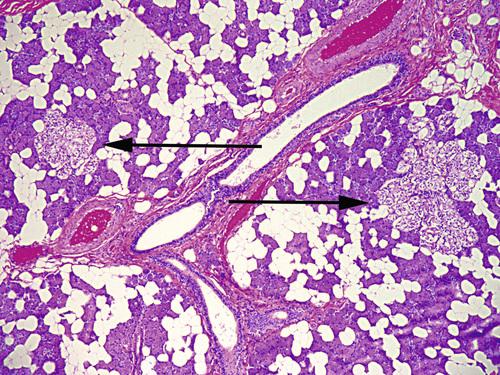

Multifocal collections of clear oncocytes (arrows) in the parotid gland. These cells have clear cytoplasm from the accumulation of glycogen.

oncocytosis